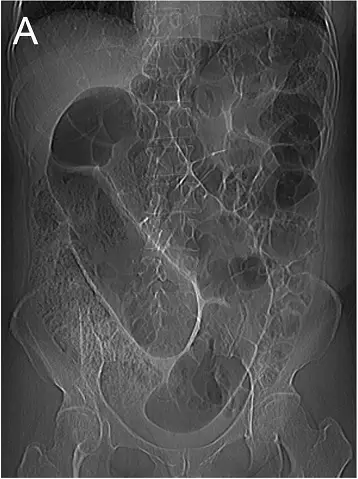

75歲老人由療養院送來,主訴腹脹,腹部X光片如圖(A),下消化道鋇劑攝影如圖(B),則其最可能的診斷為下列何者?

圖 A(腹部直立/臥位平片)

- 可見一個巨大的氣脹迂迴結腸迴盲狀構造,呈向上開口的倒 U 形,且中線處形成一明顯的中央裂隙(cleft),兩側為氣體膨脹之腸袢,未見遠端大腸明顯氣體(absent rectal gas)

- 此為典型的 “coffee bean sign”,顯示 sigmoid 結腸已沿其系膜軸捲轉,形成閉環性阻塞 (en.wikipedia.org)